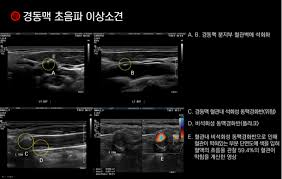

검사 후 생성된 이미지를 바탕으로 의사는 동맥의 두께, 협착 여부, 혈전 존재 여부 등을 평가하여 다양한 질병의 가능성을 진단하게 됩니다. 이러한 과정은 고도화된 기술을 활용하여 매우 정확하게 이루어지므로, 정기적인 검사는 매우 중요합니다.

동맥경화증은 혈관의 탄력성을 감소시키고, 혈관의 내벽에 지방 성분이 쌓이는 질환입니다. 경동맥 초음파 검사를 통해 경동맥의 두께와 기름기와 같은 물질의 축적 정도를 파악할 수 있습니다. 이 질환이 진행될 경우 심각한 심장병이나 뇌졸중으로 이어질 수 있기 때문에 조기 진단이 매우 중요합니다.

뇌졸중은 뇌로 가는 혈액 공급이 차단되었을 때 발생합니다. 경동맥 초음파 검사를 통해 경동맥의 협착 상태를 확인하면, 뇌졸중의 위험도를 평가하고 예방할 수 있습니다. 만약 경동맥에 심한 협착이 관찰된다면, 이에 따른 치료 및 관리가 필요합니다.